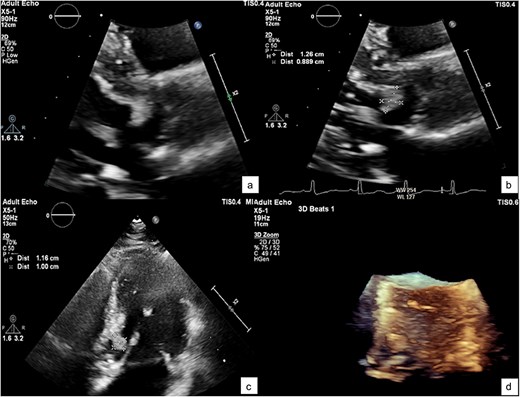

He was referred to our hospital for further evaluation by the cardiology and cardiothoracic surgery departments. On admission, he was afebrile with a heart rate of 62 beats per minute, blood pressure of 148/73 mmHg, and respiratory rate of 20 breaths per minute. No abnormalities were noted in any other system. Laboratory findings were unremarkable. An ECG demonstrated normal sinus rhythm. TTE re-evaluation revealed a normal LVEF of 72% with a 1.2 × 1 cm hypermobile cardiac mass attached to the basal anteroseptal wall near the LVOT without evidence of LVOT obstruction; there were no valvular lesions or thrombus seen (Figs 1 and 2). Coronary angiography showed normal coronary vessels. Due to its nature and clinical presentation, the patient was set for early surgical excision of the mass 3 days after admission.

A zoomed-in view of the mass with measurements of 1.2 × 1 × 0.9 cm (a–c) and in 3D echocardiography (d).